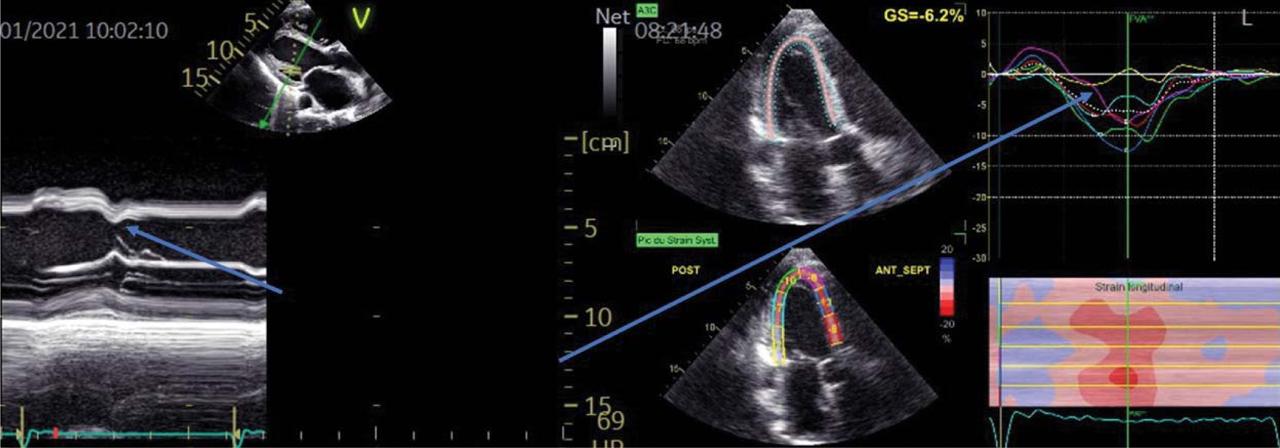

Figure 2

Look at the septal motion (or deformation): the interdependent leads to a paradoxical motion seen in M-mode and with the strain modality (yellow and light blue curves.